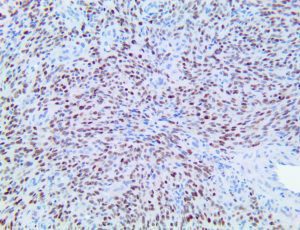

It is the ICU physician who is most likely to witness one of the deadliest manifestations of the abnormal immunological response, the cytokine storm syndrome (CSS). This response is also referred to by some as the cytokine release syndrome (CRS). CSS is characterized by continuous activation and expansion of macrophage and lymphocyte populations, which secrete large amounts of cytokines, causing the cytokine storm. This massive cytokine release is akin to hemophagocytic lymphohistiocytosis (HLH) disease, a syndrome characterized by initial unchecked and persistent activation of cytotoxic T lymphocytes and NK cells.

Clinical and laboratory manifestations of HLH include fever, enlarged liver and/or spleen, neurologic dysfunction, coagulopathy, liver dysfunction, cytopenias (i.e., low levels of erythrocytes, leukocytes, and/or platelets), hypertriglyceridemia, hyperferritinemia, hemophagocytosis, and eventually diminished NK cell activity as the immune system becomes progressively paralyzed. HLH can be familial (primary HLH) or secondary to another disease process (sHLH), such as rheumatic disease, in which it is referred to as macrophage activation syndrome (MAS, characterized by elevated ferritin).